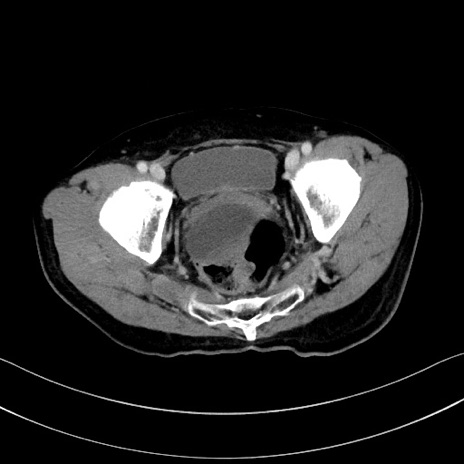

冠状断像

【症例】60歳代男性

【主訴】嘔吐

【現病歴】胃癌にて胃全摘後。食思不振が悪化し、夜中に嘔吐することがある。

【既往歴】胃癌、胃全摘、脾摘、胆摘後

【データ】WBC 5900、CRP 10.56